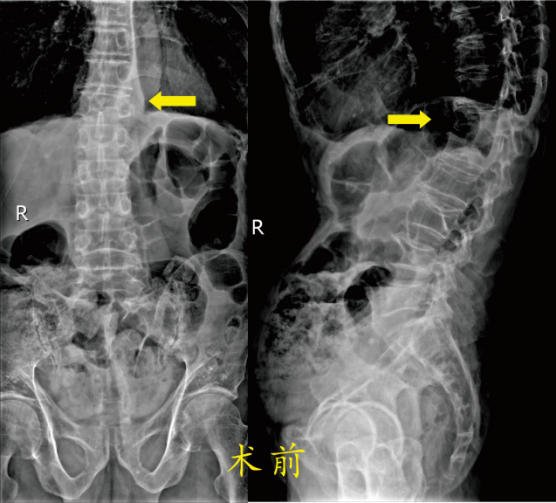

患者1: 高爷爷,男,89岁,因“摔伤致腰背部疼痛活动障碍2天”以“胸椎骨折”2024年6月1日收入骨科住院。入院诊断:1.胸椎骨折(T12),2.腰椎间盘突出,3.慢性阻塞性肺病,4.支气管哮喘,5.肺气肿,6.胸膜肥厚,7.肾结石(双侧),8.单纯性肾囊肿(左侧)。

因高爷爷患有严重的肺部疾病,在不吸氧的情况下血氧饱和度只能维持在80-90%之间,所以手术的风险很大。